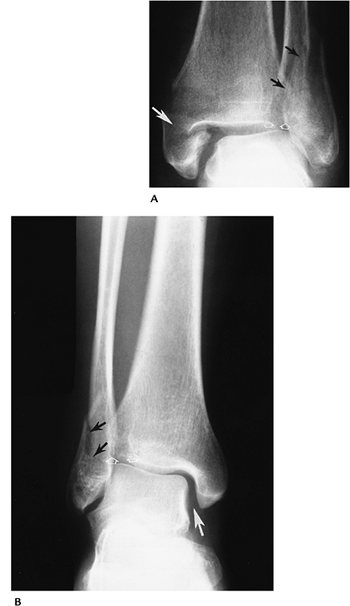

P.331

FIGURE 6-18 Pronation lateral rotation Stage IV injury with a transverse medial malleolar fracture (small arrow), disruption of the tibiofibular and interosseous ligaments (arrowhead), and a high fibular fracture (large arrow).